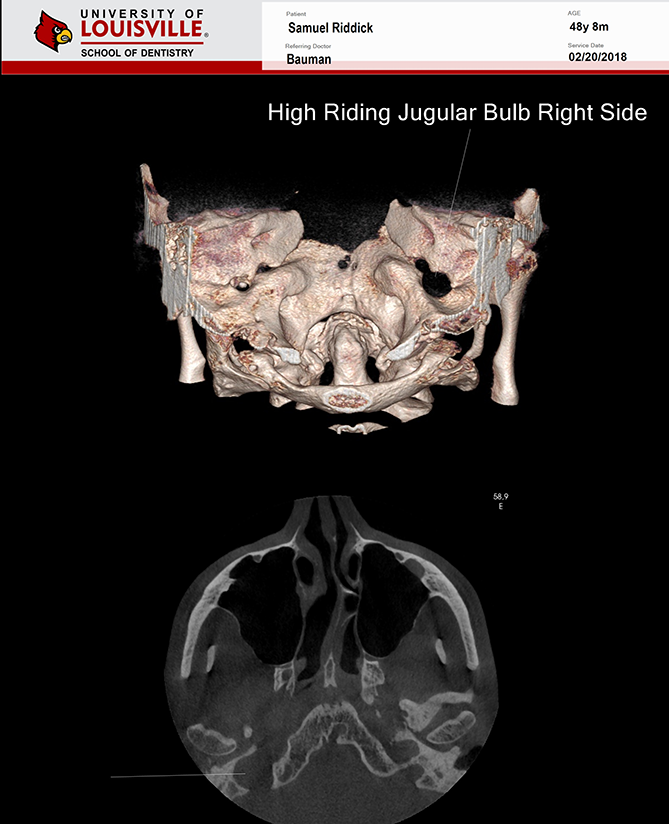

Este é um paciente masculino de 48 anos de idade e foi encaminhado para a clínica de Radiologia oral e maxilo-facial na Universidade de Louisville para uma aquisição de tomografia de feixe cônico da face para planejamento de implante.

Uma tomografia da maxila foi adquirida para avaliação do dente 21 e dos dois seios maxilares. Durante a interpretação do exame foi notado uma área ovalada, multilocular grande, bem definida, corticalizada na região retroclival prepontine. Este achado é fortemente consistente com Ecchordosis Physaliphora. Ecchordosis physaliphora é uma lesão hamartomatosa benigna congênita e pode ser encontrada em qualquer lugar da base do crânio ao osso sacrum. Também notei um forame jugular assimétrico no lado direito. Note que as margens são corticalizadas e não há sinais ou erosão / padrão mordida de traça. O aumento do forame jugular tornando-o assimétrico é fortemente consistente com Bulbo Jugular Alto. Esta variante anatômica ocorre mais comumente do lado direito. Há uma grande e fina espora óssea decorrente da parede lateral esquerda do septo nasal estendendo todo o caminho até a parede lateral esquerda da cavidade nasal.